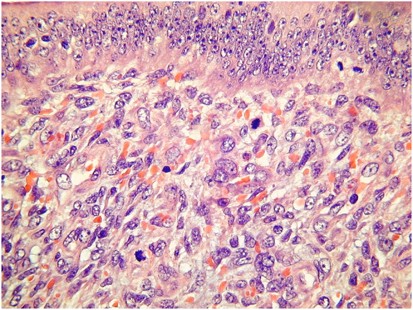

Adenosarcoma with Sarcomatous Overgrowth

Sarcomatous overgrowth is defined as the presence of pure sarcoma (without epithelial elements) comprising >25% of the tumour.1 The sarcoma is typically high grade and may be composed of rhabdomyosarcoma or undifferentiated sarcoma (Figure 11). Rarely, the sarcoma in sarcomatous overgrowth may be low grade. Sarcomatous overgrowth is typically associated with deep myometrial and vascular invasion, and is the most important prognostic factor.42